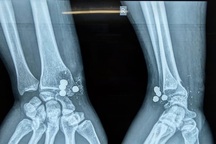

Hình ảnh chụp X-quang cho thấy nhiều viên đạn găm vào đầu cháu bé (Ảnh: Bệnh viện Sản Nhi tỉnh Ninh Bình).